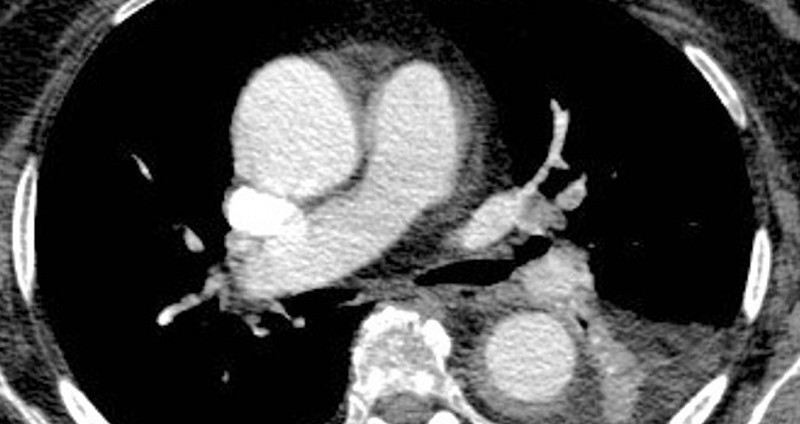

{"name":"Las 10 preguntas MIR (comentadas) que más te estrujarán el cerebro", "url":"https://www.quiz-maker.com/QPREVIEW","txt":"Varón de 78 años diabético tipo 2 que consulta por disnea y dos episodios de síncope en la última semana y refiere angina de esfuerzo no progresiva en los últimos 5 meses. En la exploración física el paciente se encuentra eupneico, TA 143\/60 mmHg, FC 78lpm, Sat O2 98%. Auscultación pulmonar con murmullo vesicular conservado y auscultación cardiaca con soplo sistólico aórtico IV\/VI que borra completamente el segundo tono, irradiado a carótidas. El paciente ingresa en la planta de cardiología y se realiza ecocardiograma transtorácico que muestra VI de dimensiones normales con hipertrofia ventricular izquierda concéntrica moderada, hipoquinesia moderada del segmento medioapical anterior y FEVI conservada. La válvula aórtica se encuentra severamente calcificada con velos engrosados y apertura visualmente restringida. El gradiente transvalvular aórtico medio es de 60 mmHg y el área valvular estimada de 0.9 cm2. Se decide realizar coronariografía diagnóstica a fin de descartar enfermedad coronaria y en la misma se objetiva: TCI (tronco coronario izquierdo) sin estenosis significativas, DA (arteria descendente anterior) proximal con estenosis severa del 70%, CX (arteria circunfleja) con dos estenosis en tándem del 60%, OM (arteria obtusa marginal) ostial con estenosis del 50% y CD (arteria coronaria derecha) con irregularidades no significativas. ¿Cuál sería la actitud terapéutica con este paciente?:, Acude a su conculta un hombre de 55 años con antecedente de trombosis venosa profunda por fiebre recurrente de semanas de evolución de hasta 38.5ºC con artralgias y artritis. En la analítica destaca elevación de PCR y anemia macrócitica. A su llegada objetiva pápulas rosadas y violáceas en cuello y tronco. La biopsia cutánea revela dermatosis neutrofílica. A este respecto sospecha sindrome de VEXAS y solicita un panel genético de enfermedades autoinflamatorias que incluye el gen UBA1. Sobre esta entidad señale la falsa:, En un estudio se pretende investigar la relación entre la exposición a hidrocarburos aromáticos y la aparición de una determinada estirpe histológica de carcinoma urotelial. Al analizar los grupos muestrales, se aprecia que difieren en la edad además de la presencia o no de su exposición a los hidrocarburos. El riesgo relativo crudo fue de 2,5. Se realiza un análisis estratificado por la edad, obteniendo un riesgo relativo en el grupo de ancianos de 3,5, y un riesgo relativo en el grupo de jóvenes de 1,7. Indique qué tipo de error se está cometiendo en este caso:","img":"https://www.quiz-maker.com/3012/CDN/97-4784253/imagen-pregunta-10-cd.jpeg?sz=1200-00000010301000005300"}